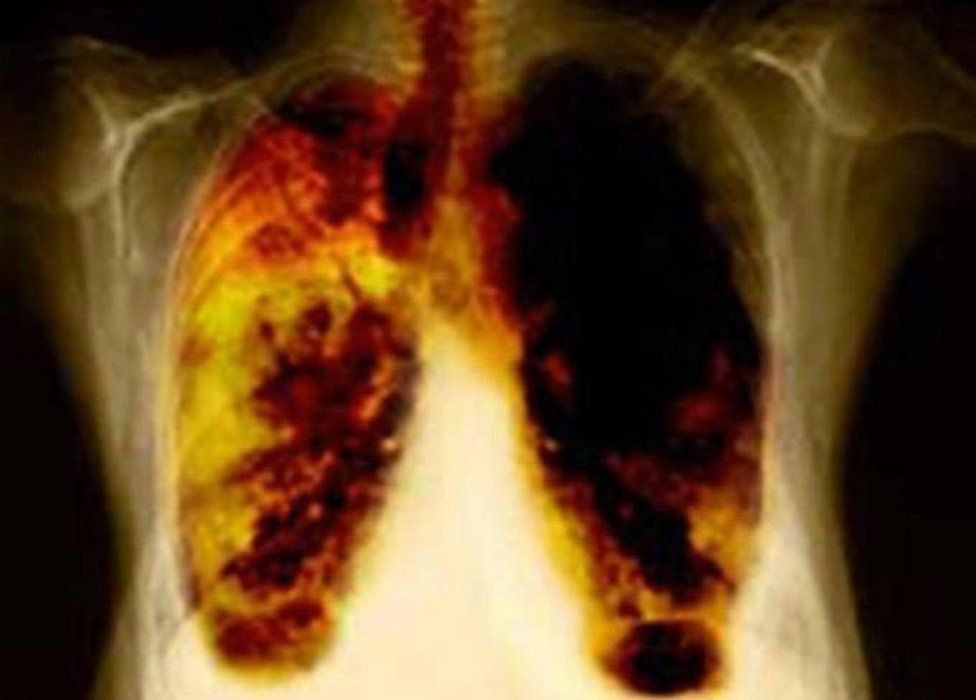

From www.bbc.co.uk

Glasgow has highest lung disease death rate in Britain BBC News Bakers Lung Death Baker’s asthma is caused by breathing in flour and grains (wheat, rye, barley, soy, or buckwheat), additives and enzymes added to bread and. Researchers examined early airway inflammation and. Among occupational lung diseases, bakers’ asthma is a relatively frequent disorder causing severe impairment of health and often combined with many social problems, especially in diseased persons, who cannot change their. Bakers Lung Death.